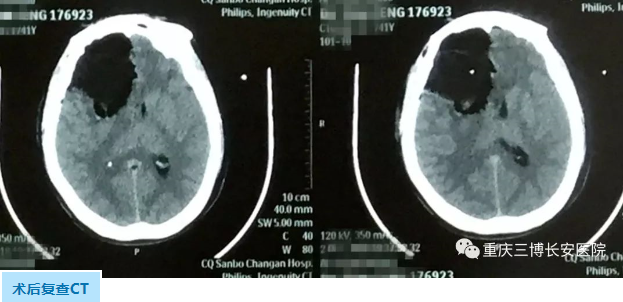

NO.1右额开颅脑肿瘤切除术

打开硬脑膜,见脑压高,切除额叶病变组织,肿瘤周边呈灰白色,质韧,与周围正常脑组织无明显界限,血供中等,显微镜下肿瘤切除满意。

术后患者恢复清醒,复查CT肿瘤切除满意。